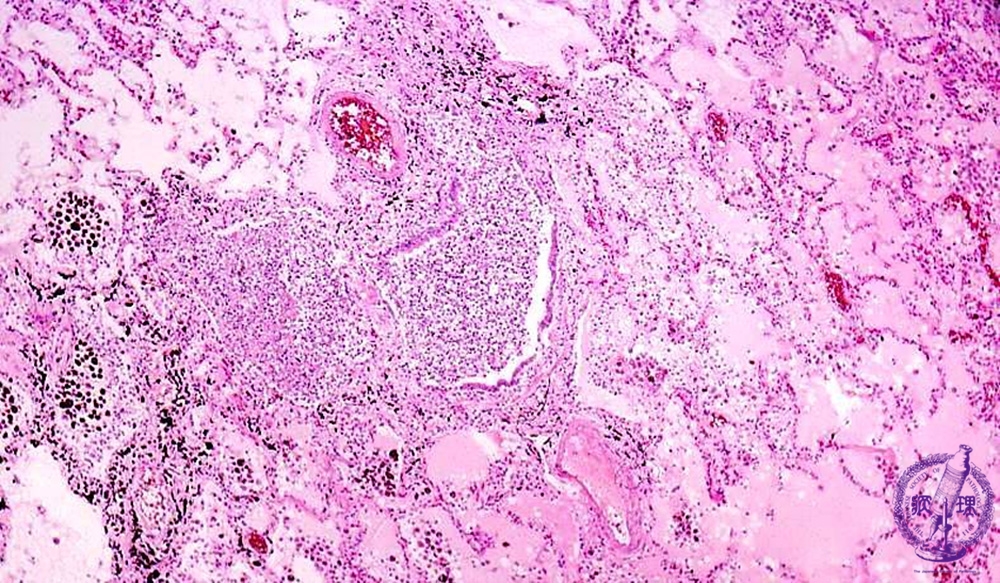

- ★(7)Bacterial pneumonia (bronchopneumonia)

Microscopic view (HE stain, low power view): The bronchiole is filled with purulent debris and surrounded by edema and an inflammatory infiltrate. Bronchial structure is obscured due to destruction of bronchial alveoli (dotted line).